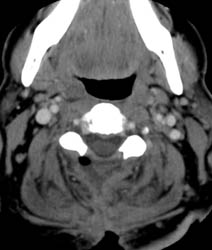

Contrast enhanced axial CT scan demonstrates unroofing

of the spinal canal from the C2 to the C7 with bilateral laminectomies and

removal of the spinous processes. There is a fluid collection without

significant rim enhancement in the post surgical bed at the C2 level,

posterior to the spinal canal. Within this, there is some air. The fluid

collection appears to extend inferiorly to the C3 level, and then a small

slit of fluid continues inferiorly to the C5 - 6 level (not shown), where it appears

to communicate with the midline incision . |